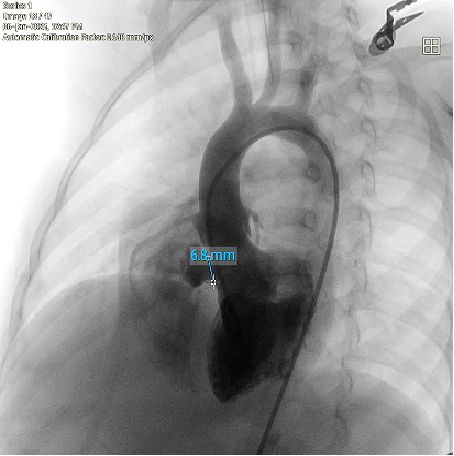

When faced with a complex congenital heart defect in a 2-year-old, how do we balance efficacy with lifelong safety? Meet a pediatric patient with a membranous ventricular septal defect (VSD) accompanied by pseudoaneurysm formation (basal width: 8.2 mm, shunt: 3.5 mm) and left ventricular false tendon—a rare and anatomically challenging scenario. Over two years of 5-time's follow-up, she was all diagnosed with typical membranous VSD, with a high-velocity left-to-right shunt (peak velocity: 5.1 m/s, gradient: 104 mmHg) and mild tricuspid regurgitation. Traditional metal occluders risk interfering with adjacent structures like the false tendon, potentially causing thromboembolism or valve dysfunction. But innovation stepped in: A memosorb fully biodegradable occluder was chosen. Why? 1. Adaptive design: Conforms to complex VSD anatomy, ensuring stability. 2. Degrades over time: Eliminates long-term risks of metal implants. 3. Preserves future options: No permanent hardware for a growing child. This case highlights the power of patient-centered innovation in congenital heart disease. Collaboration between imaging experts, interventional cardiologists, and families is key to navigating these high-stakes decisions.